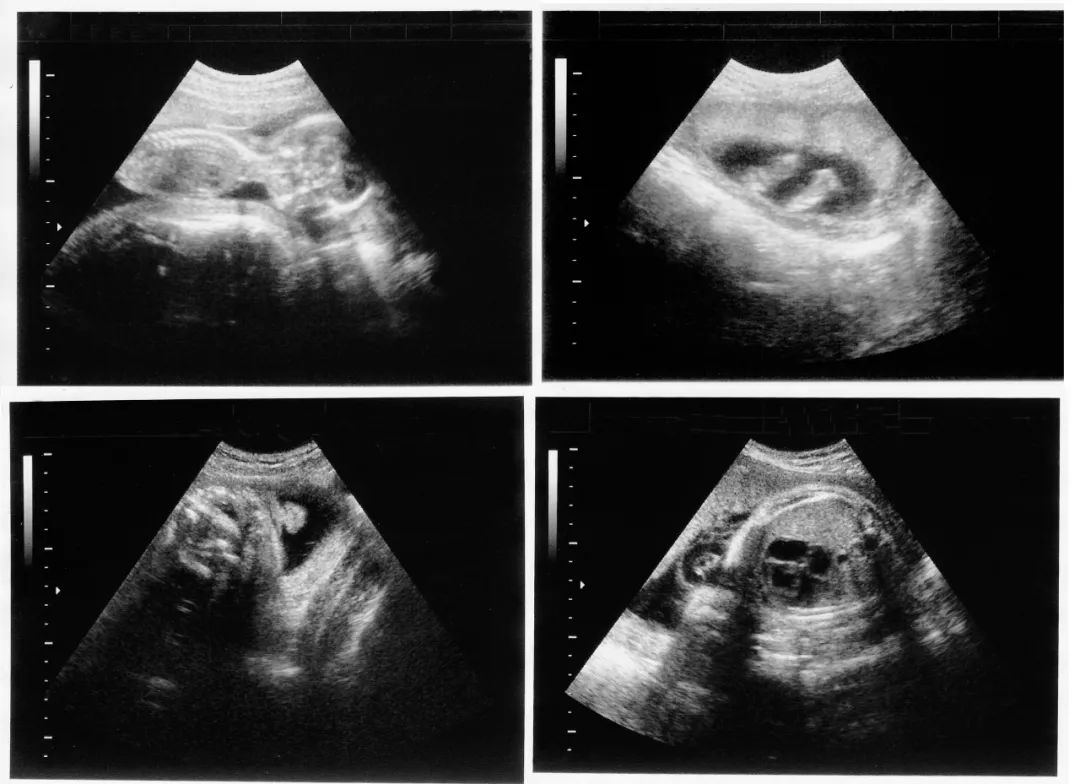

✅ NT、羊穿检查全部过关,孕26周时双胎发育良好,陈女士终于"毕业"!